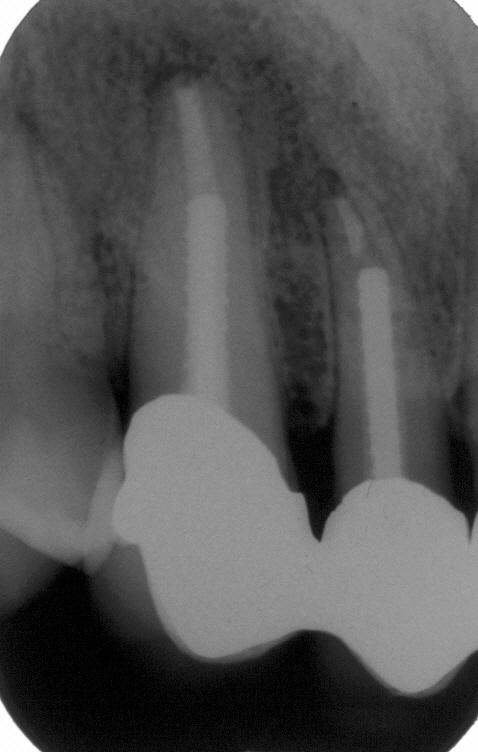

Zustand nach adhäsiver Insertion eines Titanstiftes im Januar 1997 also neun Monate nach Wurzelfüllung unmittelbar vor Eingliederung eines Langzeitprovisoriums. Die Ausheilungstendenz auf nur konservativem Wege ist deutlich sichtbar

Langzeitkontrolle vor definitivem Zahnersatz im April 1998. Die Ausheilung scheint im Vergleich zum vorherigen Bild nicht weiter voranzuschreiten